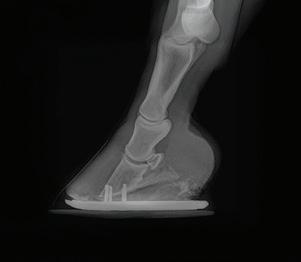

SPORT QUEENS FRONT & HIND

EC QUEENS FRONT & HIND

EC QUEENS WEDGE FRONT & HIND

RX FRONT & HIND

SPORT XLT HIND

SPORT XLT WEDGE HIND

SPORT LT HIND

EC XLT HIND

EC XLT WEDGE HIND

EC LT HIND

RX XLT HIND